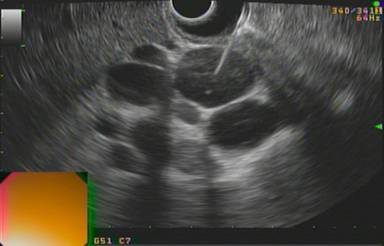

Upper endoscopy had previously shown duodenal stenosis due to circumferential ulcerated and infiltrative lesions in all cases. Facing a high probability of an unsuccessful ERCP, we discussed the possibility of endosonography-guided biliary drainage and duodenal stenting with the surgical and oncological teams. We performed the procedure following the same sequence in all cases. For the whole procedure, the patient was under general anesthesia and fluoroscopic guidance was used. A therapeutic duodenoscope (TJF-160, Olympus, Tokyo, Japan) was introduced and advanced until the duodenal bulb. A 0.035 guidewire (Jagwire®, Boston Scientific, Natick, MA, USA) was advanced through the duodenal stenosis until the proximal jejunum (Figure 1). The stenosis was dilated with a dilation balloon (CRETM Balloon Dilator, Boston Scientific, Natick, MA, USA) until 15 mm. The duodenoscope was advanced but the major ampulla could not be identified. The guidewire was left in place and the duodenoscope was removed. A linear array echoendoscope (GF UCT-140, Olympus, Tokyo, Japan; Alfa 5 processor, Aloka, Tokyo, Japan) was introduced. Endosonography examination was performed to look for the dilated common bile duct, the largest left intrahepatic duct and the presence of collateral veins. In all cases, the largest left intrahepatic ducts were smaller than 6 mm and we did not attempt the antegrade transhepatic access. The common bile duct was punctured with a 19-gauge needle (EUSN-19T, Cook Medical, Bloomington, IN, USA) (Figure 2). Bile was aspirated and contrast was injected to confirm an adequate position of the needle (Figure 3). After confirmation with fluoroscopy, a 0.035 guidewire (Jagwire®, Boston Scientific, Natick, MA, USA) was advanced through the needle into the common bile duct and the needle was retrieved. A 6-Fr cystotome (Endo Flex, Voerde, Germany) was then inserted over the guidewire to create a bilioenteric communication (Figure 4). In four patients, a partially covered biliary self-expandable metallic stent (WallFlex® 60/100 mm, Boston Scientific, Natick, MA, USA) was inserted into the common bile duct and successfully deployed, creating a choledochoduodenal fistula (Figure 5). In one patient (Patient#2), we deployed an uncovered biliary metallic stent (WallFlex® 60/100 mm, Boston Scientific, Natick, MA, USA). The echoendoscope was removed and the duodenoscope was introduced over the duodenal guidewire. A non-covered duodenal self-expandable metallic stent (WallFlex® 120/220 mm, Boston Scientific, Natick, MA, USA) was inserted over the guidewire and deployed in all patients (Figures 6 and 7).

Figure 2. Common bile duct punction. |